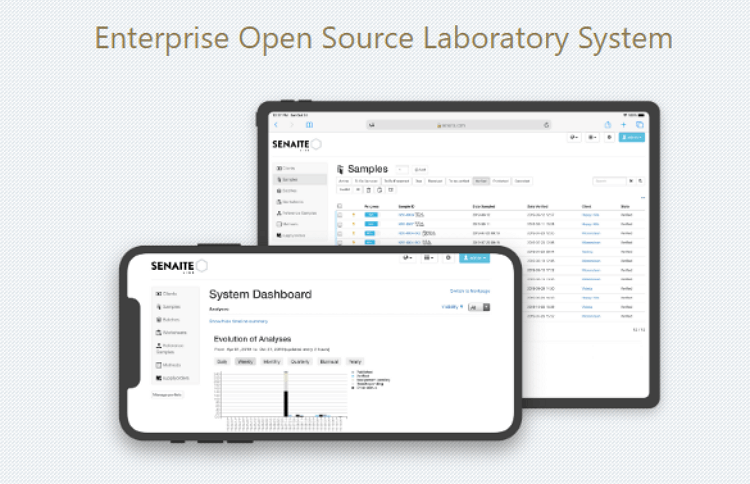

Enterprise Grade Laboratory Software

Senaite Lab is an open-source laboratory information management system (LIMS) designed specifically for managing laboratory workflows. It provides comprehensive functionalities for sample management, test request tracking, result recording, instrument integration and reporting.

With its user-friendly interface and robust features, Senaite Lab helps streamline laboratory operations, improve data accuracy, and enhance overall efficiency in testing laboratories.

Username : mrakftech Password : Senaite@0786

Full Demonstration Video of Enterprise LIS Software

Salient Features

- Sample management.

- Test Requests Mgmt.

- Result Management.

Scalability

Configurable and scalable, making suitable for various types of labs

Interoperability

Interoperability with other lab systems through interfaces and protocols.